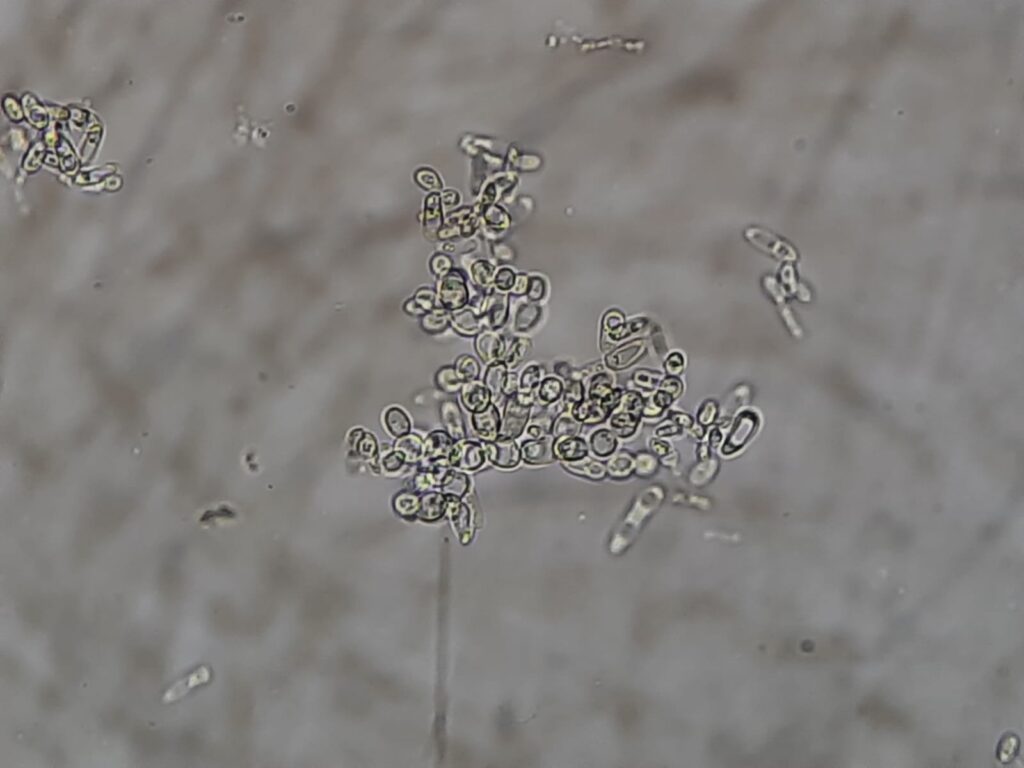

- Microscopic Appearance: Produces ovoid or elongated ellipsoidal budding cells, often described as having a “match-stick” or “long-grain rice” appearance.